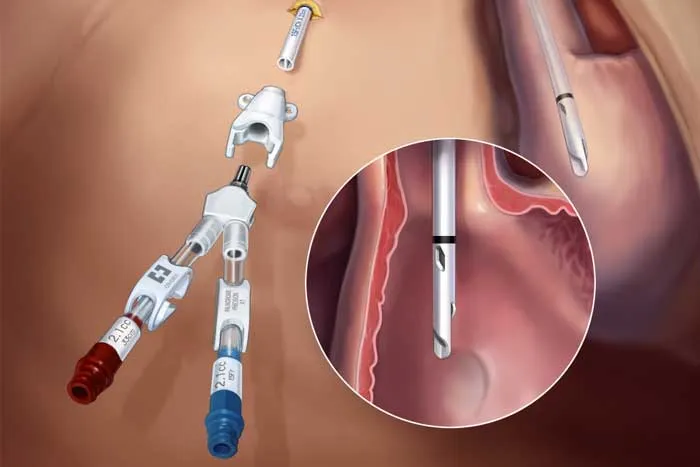

A hemodiafiltração pode aumentar significativamente a depuração de diversos medicamentos, levando a subdosagem quando usamos protocolos baseados em hemodiálise convencional. Entender a farmacocinética da droga e a prescrição da HDF é essencial para evitar falha terapêutica e ajustar corretamente as doses.